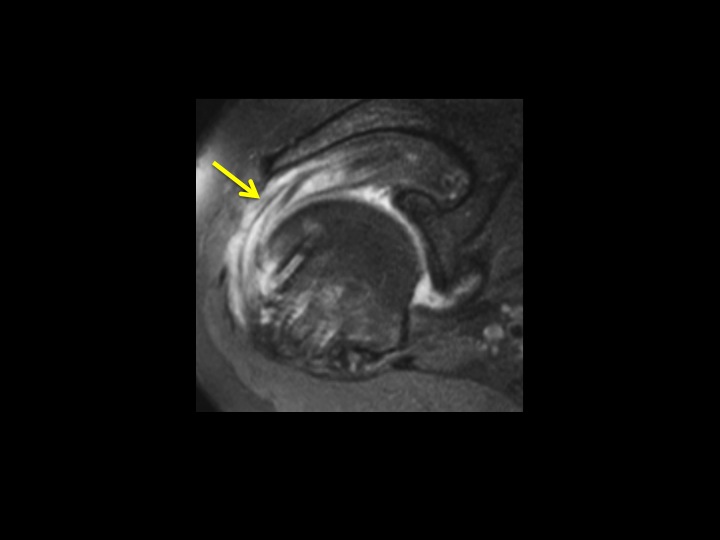

67 yr old female 1 year post RCR with shoulder pain + instability

This is always a source of confusion. There are 4 bioabsorbable anchors: 3 entering anterior to posterior at the supraspinatus insertion, 1 related to biceps tenodesis. There is a wide zone of Dark T1/Bright T2 signal with bone resorption surrounding the cuff fixations screw, but not the biceps tenodesis screw (red arrows). The supraspinatus tendon is thick and frayed, but intact. There is partial tearing of the infraspinatus and a small intrasubstance tear at the subscap insertion (yellow arrows). To what extent is the lysis surrounding these screws abnormal (there is some normal degree of lysis as the screws resorb, extrapolating from tunnel widening with ACL graft fixation). Would you report this? What would you say?